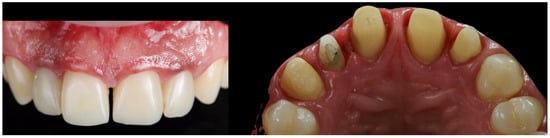

A master model was generated upon which a monolithic zirconia framework was fabricated and subsequently layered with feldspathic ceramic. A clinical try-in was conducted to assess the passive fit, aesthetic parameters, and functional integration of the definitive restorations. Final cementation was performed using a conventional glass ionomer luting agent (Ketac Cem Easy Clean, 3M Italia SRL, Milan, Italy, Figure 17).

Figure 17. Anterior guidance development (laboratory phases).

The patient was subsequently enrolled in a structured periodontal and prosthetic maintenance programme, with follow-up evaluations scheduled at four-month intervals to monitor periodontal health, occlusal stability, and the integrity of the prosthetic components (Figure 18, Figure 19 and Figure 20).

Figure 18. Final intraoral image.

Figure 19. Intraoral image at four-year follow-up.

At the four-year follow-up, clinical evaluation demonstrated stable soft and hard tissues, with no biological or mechanical complications observed throughout the entire follow-up period.

At the four-year follow-up, the clinical situation remained stable and asymptomatic. Periodontal evaluation revealed probing depths within physiological limits, a low plaque index (7%), and minimal bleeding on probing (8%), all consistent with a healthy periodontal environment. Radiographic assessment confirmed the maintenance of alveolar bone levels without signs of resorption. The patient’s reduction in tobacco use and adherence to four-month maintenance therapy intervals likely played a pivotal role in sustaining these outcomes. The four-year follow-up also confirmed the clinical stability of the treatment, both occlusally and periodontally, with a significant improvement in clinical indices and complete patient satisfaction. Masticatory function remained effective, the deep bite was corrected, and the interincisal diastema was successfully closed, resulting in a harmonious and stable aesthetic outcome. The final decision to fabricate individual crowns was justified by the favourable tissue response and the occlusal stability achieved.